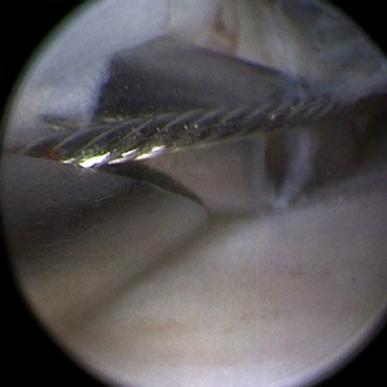

En el Journal of Oral and Maxillofacial Surgery Dr. Daniel Jerez publica adaptación a la técnica de discopéxica de Yang

El Dr. Daniel Jerez, cirujano maxilofacial y Subdirector Académico de Clínica Bupa Santiago, publicó en el mes de julio, en la prestigiosa revista especializada Journal of Oral and Maxillofacial Surgery (JOMS), un artículo que describe una modificación a la técnica de discopéxica del Dr. Yang (China).

El paper que realizó en conjunto a los doctores German Laissle, Carlos Fuenzalida y Sergio Uribe , tiene por nombre “Modification to Yang’s Arthroscopic Discopexy Technique for Temporomandibular Joint Disc Displacement: A Technical Note”, y ahonda en la adaptación a esta técnica, donde se realiza una doble sutura para efectuar la recaptura discal o discopexia.

Respecto a la técnica antes mencionada, el Dr. Jerez manifestó que “es compleja artroscópica, mínimamente invasiva y tiene como objetivo principal devolver la función articular, evitar la progresión de la osteoartrosis, reducir el dolor y mejorar la dinámica mandibular. Esta técnica se realiza muy poco, pues técnicamente es muy difícil llevarla a cabo y además requiere instrumental específico”.

DR. DANIEL JEREZ Cirujano Maxilofacial Subdirector Académico Clínica Bupa Santiago

Puntualmente, la modificación sugerida por el cirujano maxilofacial de Clínica Bupa Santiago dice relación con llevar a cabo esta técnica, pero sin necesidad de utilizar un instrumental determinado, lo cual según expresa “es mucho más estable a largo plazo y ha demostrado mejores resultados en la evidencia, ya que al ser artroscópica es una cirugía mínimamente invasiva, poco riesgosa y sin cicatriz”.

Para revisar el detalle de esta publicación y en qué consiste la modificación, los invitamos a hacer clic aquí.